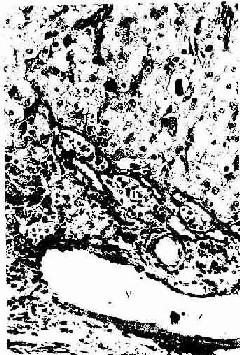

成熟卵泡排卵后,残留在卵巢内的卵泡壁塌陷,卵泡膜内的血管和结缔组织伸入颗粒层。在LH的作用下。卵泡壁的细胞体积增大,分化为一个体积很大并富含血管的内分泌细胞团,新鲜时呈黄色,称为黄体(corpus luteum)(图17-1)。颗粒细胞分化为粒黄体细胞(granular lutein cell),膜细胞分化为膜黄体细胞(theca lutein cell)。粒黄体细胞较大,呈多角形,染色较浅,数量多;膜黄体细胞较小,圆形或多角形,染色较深,数量少,分布于黄体的周边部(图17-9)。这两种细胞具有分泌类固醇激素细胞的结构特征,细胞内有丰富的滑面内质网和管状嵴的线粒体,还有脂滴和黄色脂色素。黄体的主要功能是分泌孕激素和一些雌激素,前者由粒黄体细胞分泌,后者主要由两种细胞协同分泌。

图17-9 人卵巢黄体细胞 HE×400

G粒黄体细胞 T膜黄体细胞V血管

黄体的发育因卵细胞是否受精而差别甚大。卵细胞若未受精,黄体仅维持2周,称月经黄体(corpus luteum of menstruation),黄体细胞迅速变小和退化,渐被结缔组织取代,称为白体(corpus albicans)。卵细胞若受精,黄体在胎盘分泌的人绒毛膜促性腺激素(HCG)的作用下继续发育增大,直径可达4~5cm ,称妊娠黄体(corpus luteum of pregnancy)。妊娠黄体可保持6个月,以后也退化为白体。妊娠黄体的粒黄体细胞还分泌松弛素(relaxin),它可使妊娠子宫平滑肌松弛,以维持妊娠。